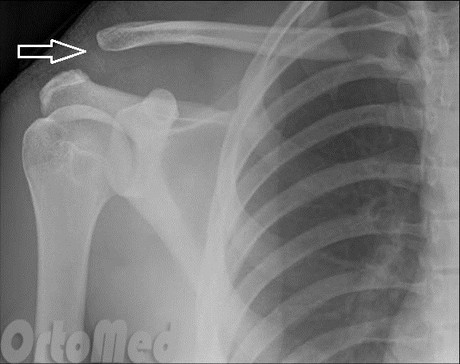

ПІСЛЯ АВТОМОБІЛЬНОЇ АВАРІЇ НА РЕНТГЕНОГРАМІ ВИЯВЛЕНО ПЕРЕЛОМ КІСТКИ В ДІЛЯНЦІ ХІРУРГІЧНОЇ ШИЙКИ. ЯКА КІСТКА МАЄ ТАКУ ШИЙКУ?

НА ЯКИЙ СУГЛОБ ВКАЗУЄ СТРІЛКА НА РЕНТГЕНОГРАМІ? КІСТКИ ЯКОГО ВІДДІЛУ СКЕЛЕТУ ВІН З'ЄДНУЄ?

варіанти відповідей

ГРУДНИННО-КЛЮЧИЧНИЙ С.

ПЛЕЧОВИЙ С.

НАДПЛЕЧОВО-КЛЮЧИЧНИЙ С.

АКРОМІАЛЬНО-КЛЮЧИЧНИЙ С.

КІСТКИ ВЕРХНЬОЇ КІНЦІВКИ

КІСТКИ ТУЛУБА І ВЕРХНЬОЇ КІНЦІВКИ